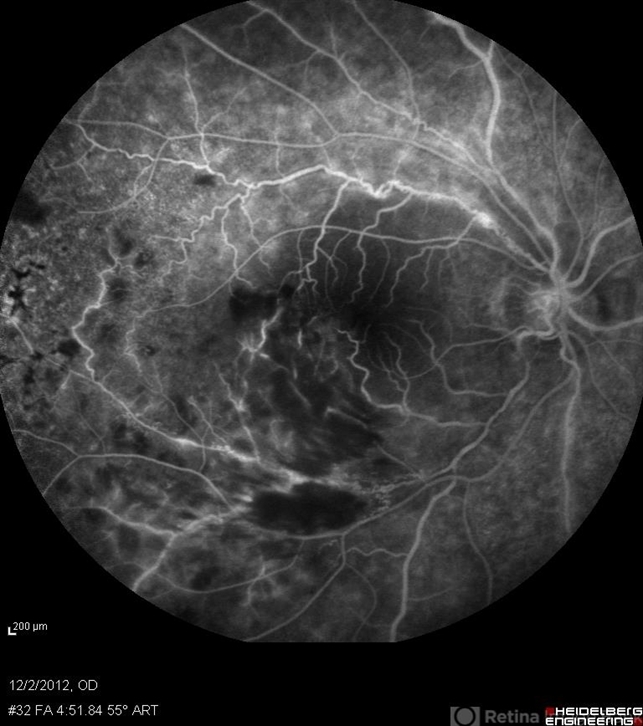

- retinal vasculitis, branch retinal vein occlusion (BRVO)

- Solmaz Shahmohammad, Negah Eye Center, Tehran

- Heidelberg Spectralis

- Late phase FA of the right eye of a 23-year-old man with retinal vasculitis and branch retinal vein occlusion (BRVO) due to Behcet's disease .